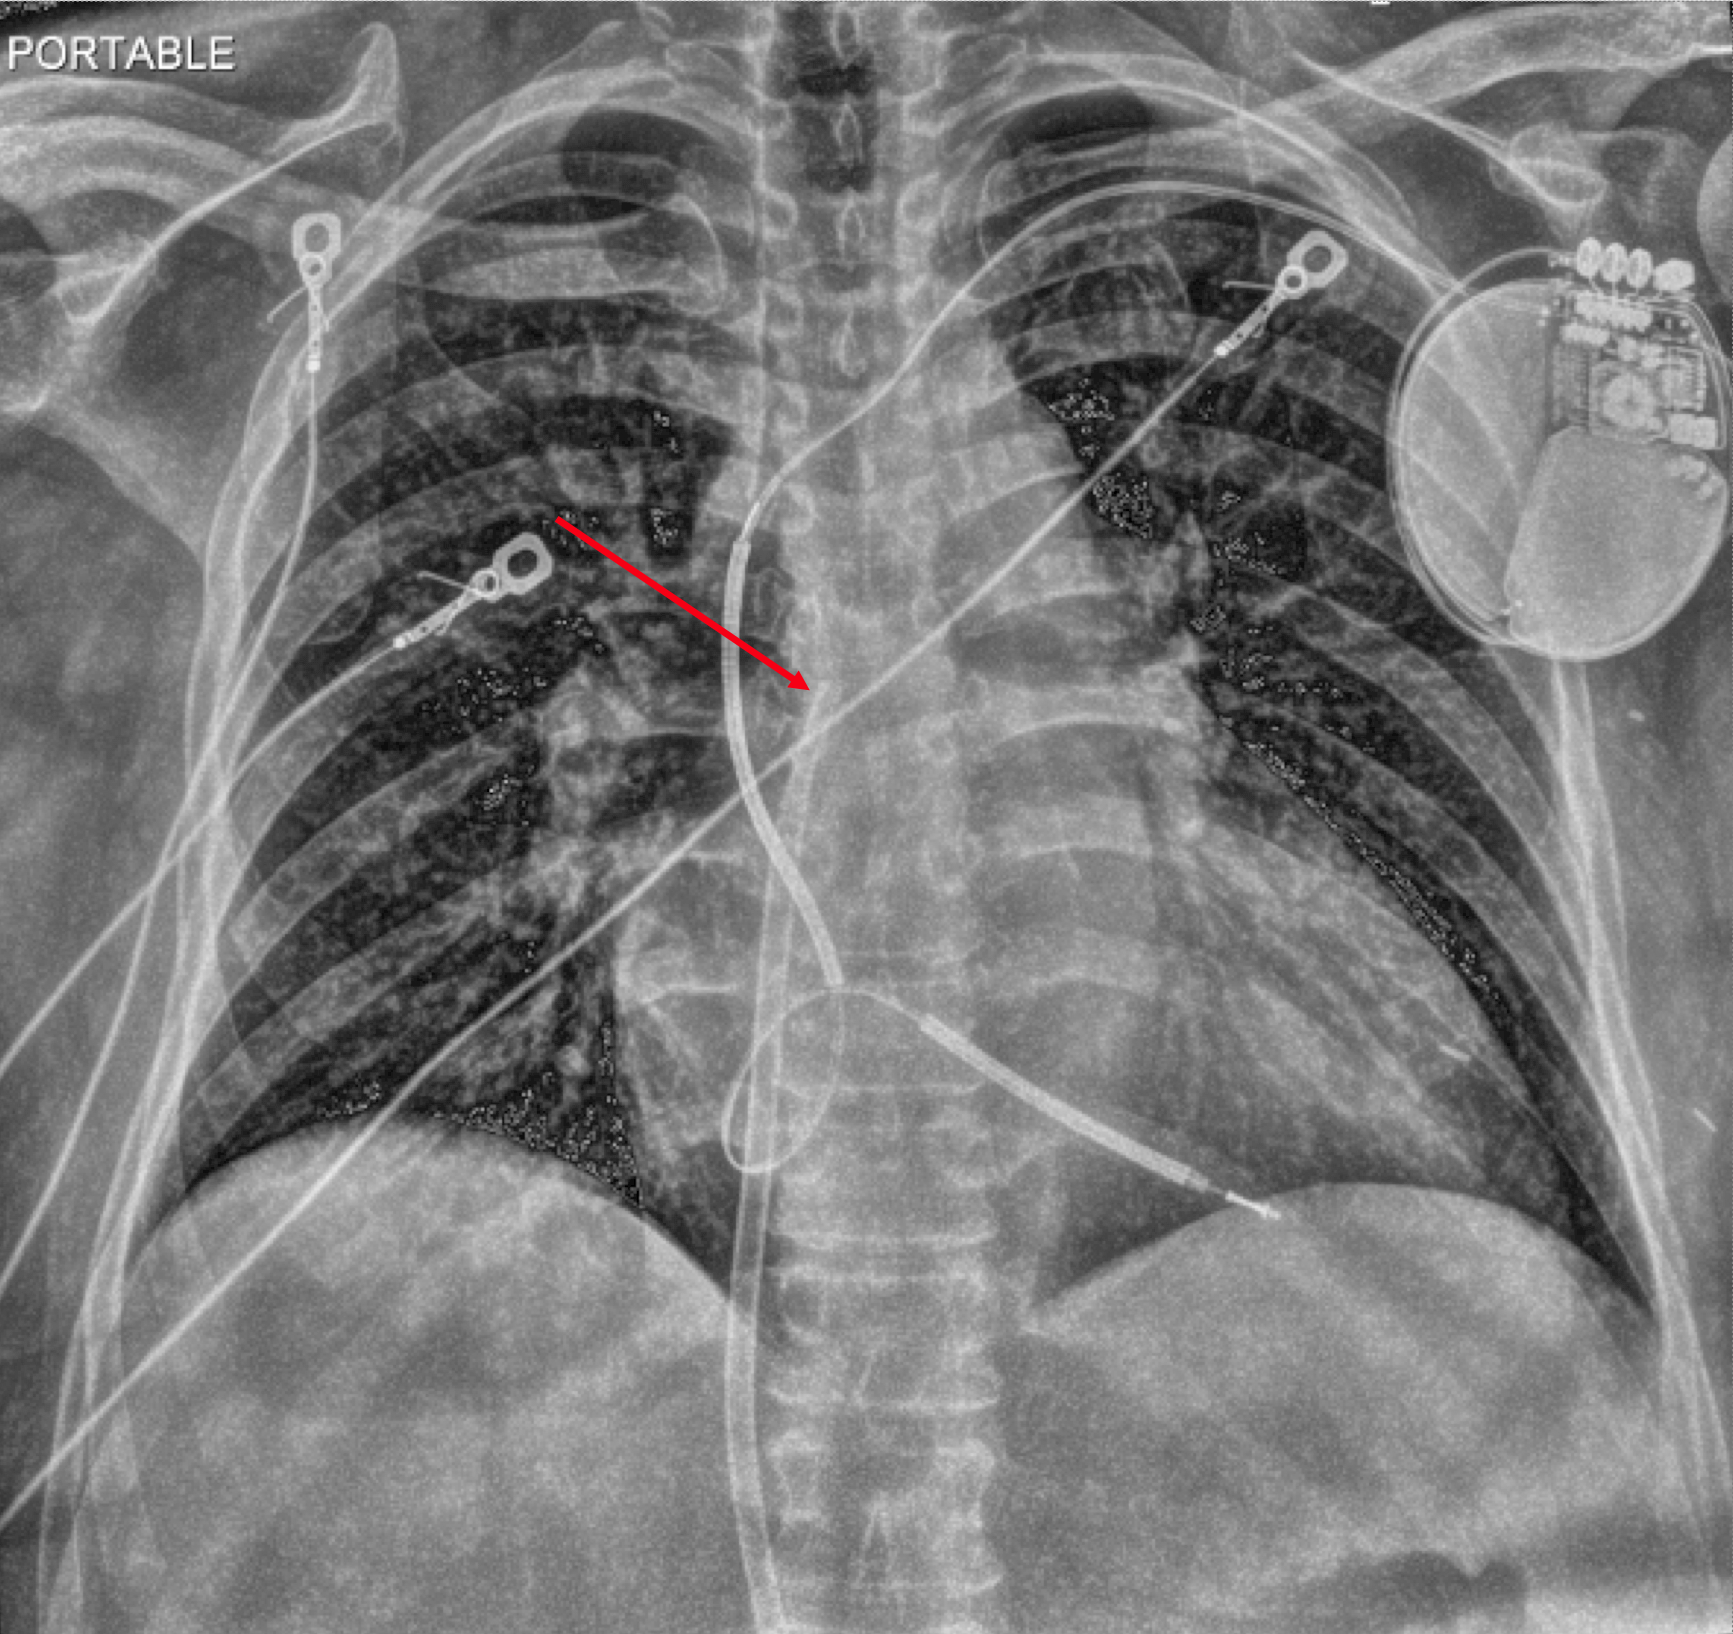

Case: A 61-year-old woman with heart failure with reduced ejection fraction (EF 25%), end-stage renal disease on hemodialysis, and a history of breast cancer presented with a malfunctioning hemodialysis catheter. After unsuccessful local alteplase, interventional radiology performed a left femoral hemodialysis catheter exchange. Within one hour post-procedure, the patient developed syncope, hypotension (60/40 mmHg), tachycardia (120 bpm), and reported chest discomfort, weakness, and lightheadedness. Bedside electrocardiogram showed sinus tachycardia with electrical alternans. Emergent echocardiography revealed a moderate circumferential pericardial effusion with right atrial systolic and right ventricular diastolic collapse, distended inferior vena cava, and marked respirophasic variation of atrioventricular inflow velocities, consistent with cardiac tamponade. Chest radiography suggested the catheter tip abutting the right atrial free wall. The delayed perforation was likely due to catheter migration and erosion. Despite aggressive fluid resuscitation and norepinephrine infusion (up to 35 mcg/hr), the patient remained unstable. Bedside pericardiocentesis drained approximately 700 mL of blood, resulting in rapid hemodynamic improvement and discontinuation of vasopressors within one hour. Computed tomography confirmed the catheter tip’s proximity to the right atrial wall. Cardiothoracic surgery determined that surgical intervention was unnecessary as the perforation had sealed spontaneously.